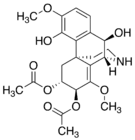

Oripavine derivatives

Thienorphine

- 7-PET

- Acetorphine

- Alletorphine (N-allyl-noretorphine)

- BU-48

- Buprenorphine

- Buprenorphine-3-glucuronide

- Cyprenorphine

- Dihydroetorphine

- Etorphine

- Homprenorphine

- 18,19-Dehydrobuprenorphine (HS-599)

- N-cyclopropylmethylnoretorphine

- Nepenthone

- Norbuprenorphine

- Norbuprenorphine-3-glucuronide

- Thevinone

- Thienorphine

Structures

| Oripavine derivatives | ||||

|---|---|---|---|---|

7-PET 7-PET |

Acetorphine Acetorphine |

Alletorphine Alletorphine |

BU-48 BU-48 |

Buprenorphine Buprenorphine |

Cyprenorphine Cyprenorphine |

Dihydroetorphine Dihydroetorphine |

Etorphine Etorphine |

Homprenorphine Homprenorphine |

18,19-Dehydrobuprenorphine 18,19-Dehydrobuprenorphine |

N-cyclopropylmethylnoretorphine N-cyclopropylmethylnoretorphine |

Nepenthone Nepenthone |

Norbuprenorphine Norbuprenorphine |

Thevinone Thevinone |

Thienorphine Thienorphine |